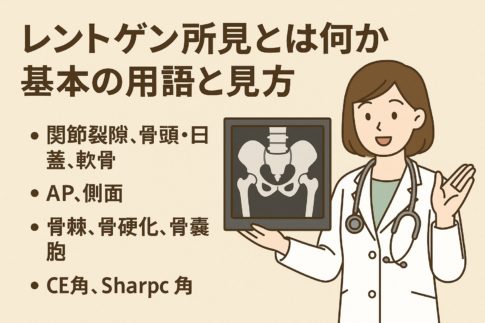

・整形外科・リハビリの診療内容

→ 検査・治療の流れの目安(レントゲン・理学療法など)